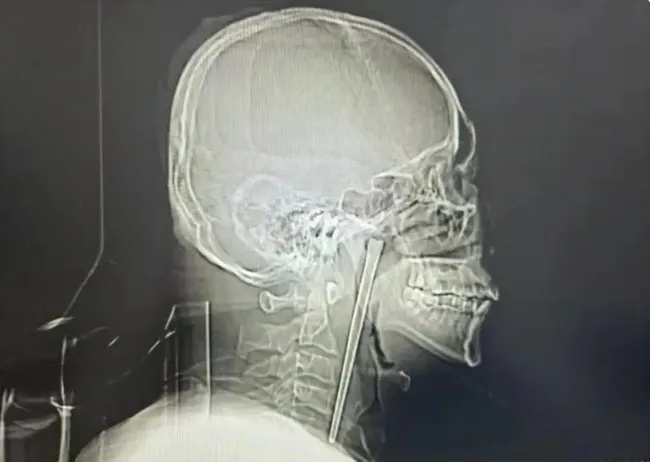

중국 랴오닝성 다롄시의 한 남성이 8년 전 식사 중 실수로 삼킨 길이 12㎝의 금속 젓가락을 최근 제거 수술로 빼냈다. 왕씨는 당시 호흡에 이상이 없어 의사의 절개 수술 권유를 거부했고, 이후 8년간 이물감을 참으며 생활했다.

최근 통증이 심해지자 병원을 찾은 왕씨는 정밀 검사 결과 젓가락이 목 안쪽 연구개 부위에 박혀 있었음을 확인했다. 의료진은 주변 점막 손상이 없고 성대 기능이 정상이라고 설명했으며, 구강을 통한 최소 침습 수술로 젓가락을 성공적으로 제거했다.

술 마시다 목에 12㎝ 젓가락 박혔다…8년 버티던 남성 결국